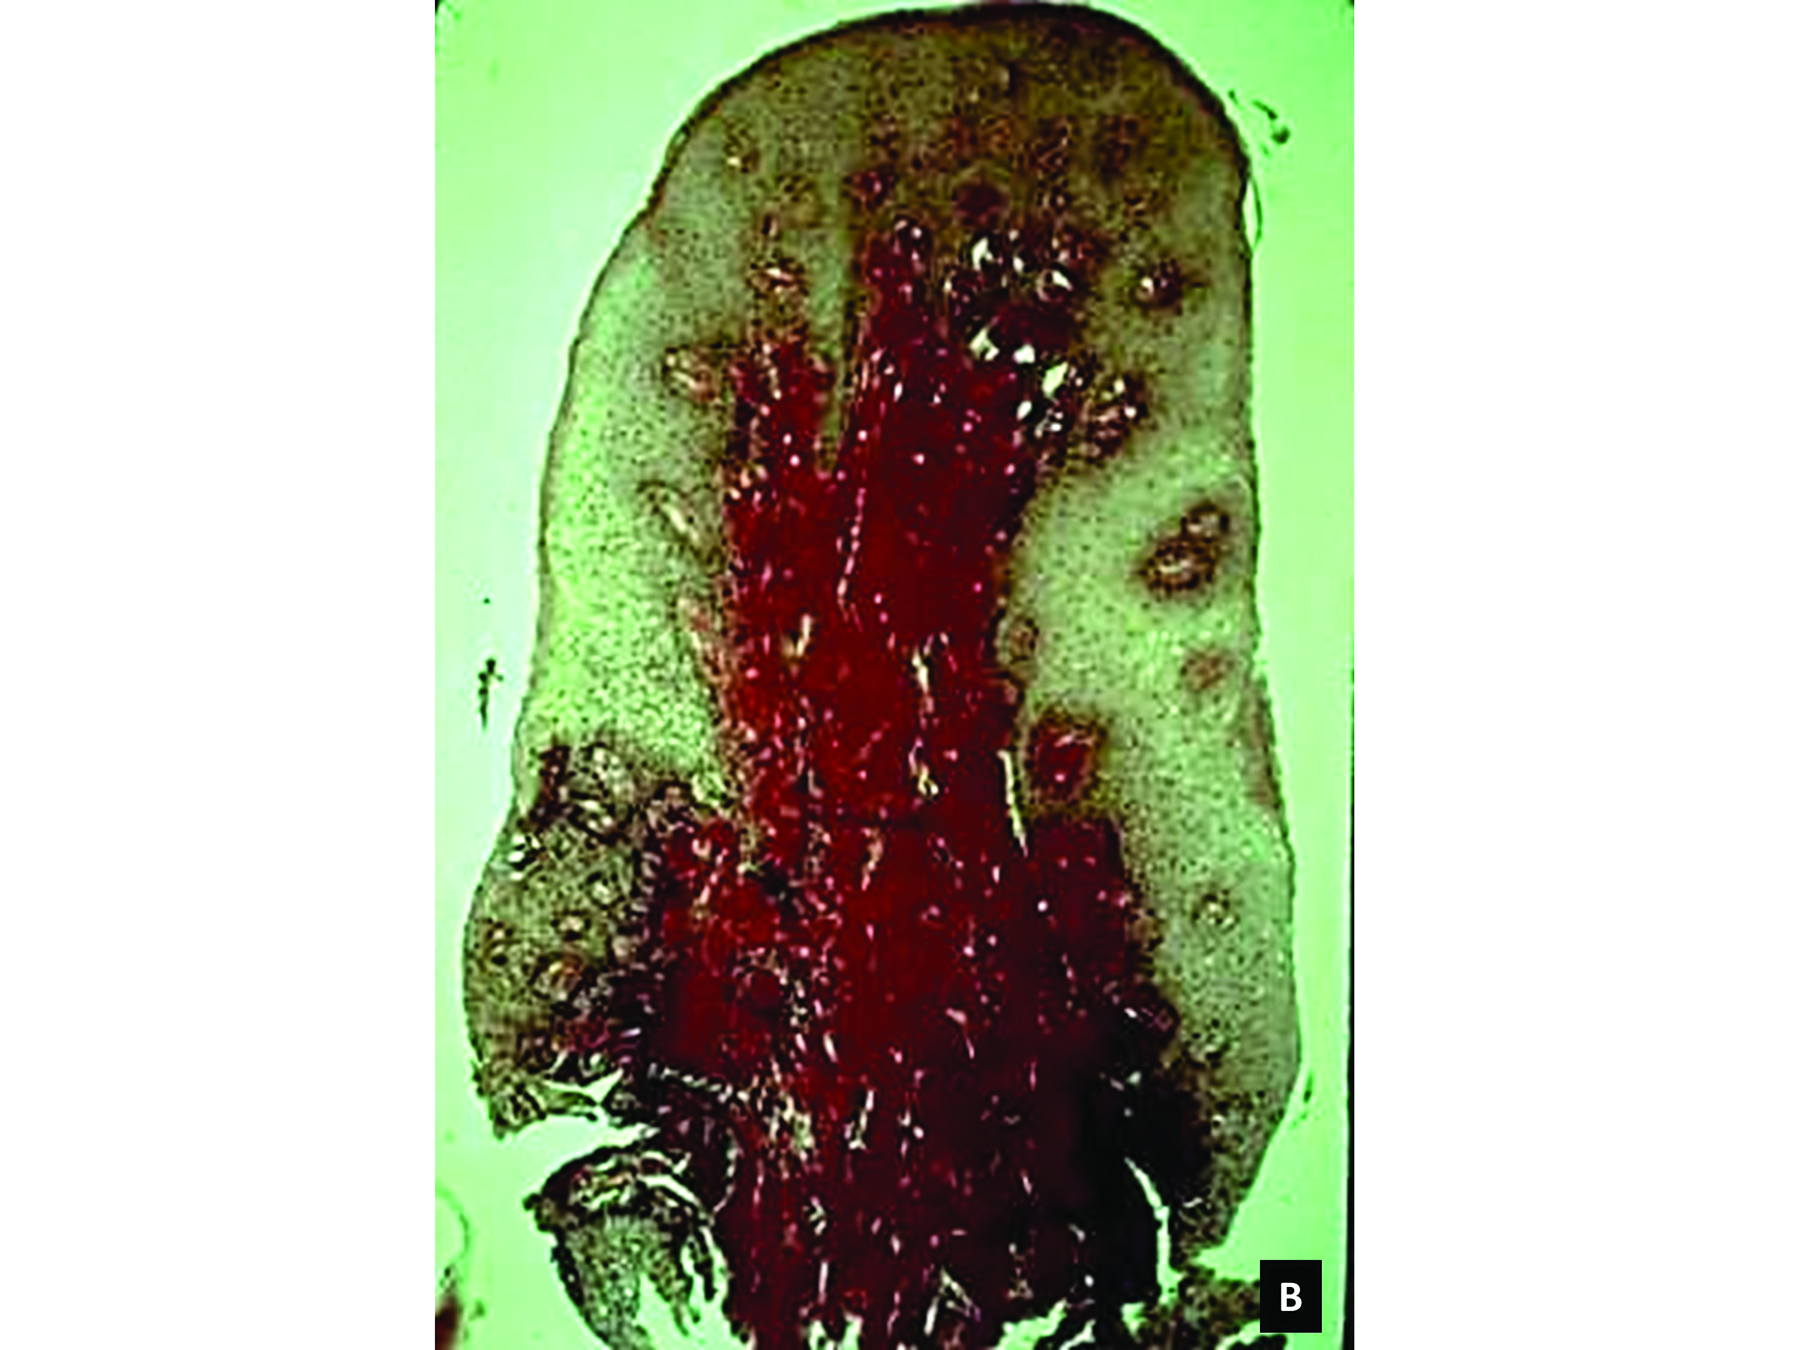

Bleeding: not a good predictor of disease activity. Bleeding on probing (BOP) represents an inflammatory infiltrate in the connective tissue, a reduction of collagen, and ulceration of the pocket's epithelial lining (Figure 2 and Figure 3).18 However, bleeding does not indicate the severity of periodontal lesions, and BOP is not a good predictor of disease activity.19 The term "disease activity" denotes there is ongoing clinical attachment and/or bone loss. Conversely, the absence of BOP is a good forecaster of clinical health and long-term tooth retention.19 Thus, BOP is an excellent indicator of the need for therapy, and its elimination is an important clinical endpoint.

Fig 2. Gingival biopsy from a site that bled upon probing. Note an inflammatory infiltrate (dark area) and reduction of collagen (whitish area).

Figure 2

Fig 3. Gingival biopsy from a site that did not bleed upon probing. Note there is no inflammatory infiltrate and the collagen (reddish area) is intact. (Fig 2 and Fig 3 are courtesy of Jack Caton, DDS.)

Figure 3